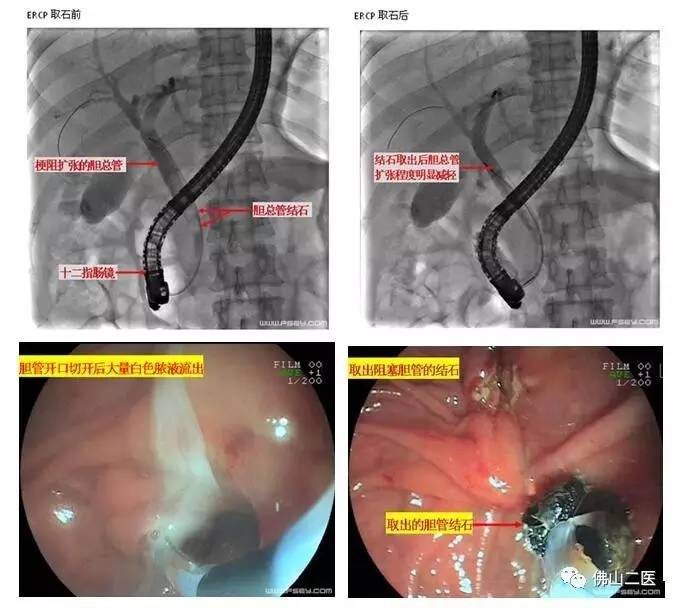

消化内科陈渭副主任医师紧急为患者进行了内镜微创治疗。内镜经过口腔、胃肠道到达胆总管开口,作了一个约半厘米长的小切口,引出大量脓液并取出堵塞胆管的多枚结石,治疗用时仅半小时。治疗结束时患者体温已降落至38℃,血压回升至110/80mmHg,腹痛也明显缓解。第二天黄疸就明显消退,恢复进食,现已康复出院。

ERCP是经内镜逆行胰胆管造影术的简称,因为可行切开、扩张、引流、取石等内镜下治疗操作,已成为胆胰疾病的重要微创治疗手段,也是目前公认的胆总管结石的首选治疗方法。目前我院消化内科已全面开展ERCP诊疗操作,可进行胆管结石、胆管癌、胰头癌、慢性胰腺炎等各类胆道、胰腺疾病的微创诊治,创伤小,恢复快,尤其适合不能耐受或不愿行手术治疗的患者,疗效显著,深得患者欢迎和认可。